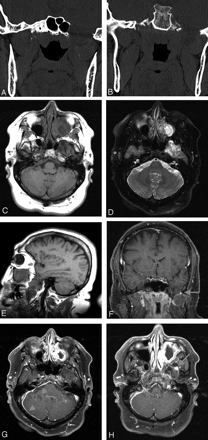

Subsequent MR imaging of the skull base demonstrated a transalar cephalocele protruding approximately 2.5 cm inferiorly through the left greater sphenoid defect. This cephalocele was bounded superiorly and posteriorly by the carotid canal and inferiorly by the pharyngeal recess and anteriorly by the left maxillary sinus. The cephalocele contained meninges as well as brain tissue. There was associated widening of the left temporal horn and the inferior temporal sulcus, with protrusion of a portion of the inferior aspect of the left temporal lobe through the sphenoid defect. On postcontrast images, there was irregular peripheral enhancement of the meningoencephalocele along its margins (Fig 1). Contrast enhancement along the pachymeninges of the posterior fossa on the right was also noted. The patient subsequently underwent successful endoscopic ethmoidectomy and middle meatal antrostomy.

Coronal CT images (A and B) disclose the large bony defect encompassing the region of the foramen ovale and most of the left greater sphenoid wing. Axial T1- and T2-weighted images at the level of the internal auditory canal (C and D) demonstrate the transalar encephalocele presenting prolonged T1 and T2 signals and a heterogeneous lesion centered on the left maxillary antrum presumably related to the known history of Wegener granulomatosis. Sagittal T1-weighted image (E) better shows the left temporal lobe tip insinuating through the bony defect into the masticatory space. Coronal T1-weighted contrast-enhanced image with fat saturation (F) demonstrates again the encephalocele and irregular foci of contrast enhancement along the peripheral portion of the encephalocele (arrows). Axial T1-weighted contrast-enhanced images with fat saturation (G and H) show intense enhancement of the mucosa of the inspissated and inflamed left maxillary sinus. There is also linear dural thickening and enhancement of the dura within the posterior fossa along the medial aspect of the right temporal and occipital bones extending posterior to the clivus (arrowheads), possibly also related to Wegener granulomatosis. A focus of enhancement in the anterior and inferior portion of the encephalocele is again appreciated (arrow).